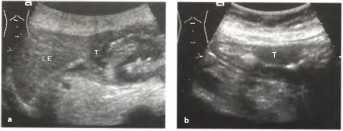

В качестве примера визуализации патологии с помощью сонографии можно привести гастросонорграммы опухолей антрального отдела желудка в сравнении с нормальной ЭХО-картиной органа.

Рис. 20. b а Карцинома желудка: опухоль (Т) антрального отдела со сложной эхоструктурой. b Полиповидная опухоль (Т), гистологически идентичная с карциноидом.

Рис. 22. Осмотр антрального отдела желудка на поперечном сечении: а, b Плоская асимметричная полиповидная опухоль (Т), глубоко инвазирующая стенку желудка и прорастающая ее: стромальная опухоль ЖКТ (GIST), в данном случае злокачественная и уже с метастазами. А - антральная часть, b Эндоскопическая картина. Результаты биопсий были отрицательными.